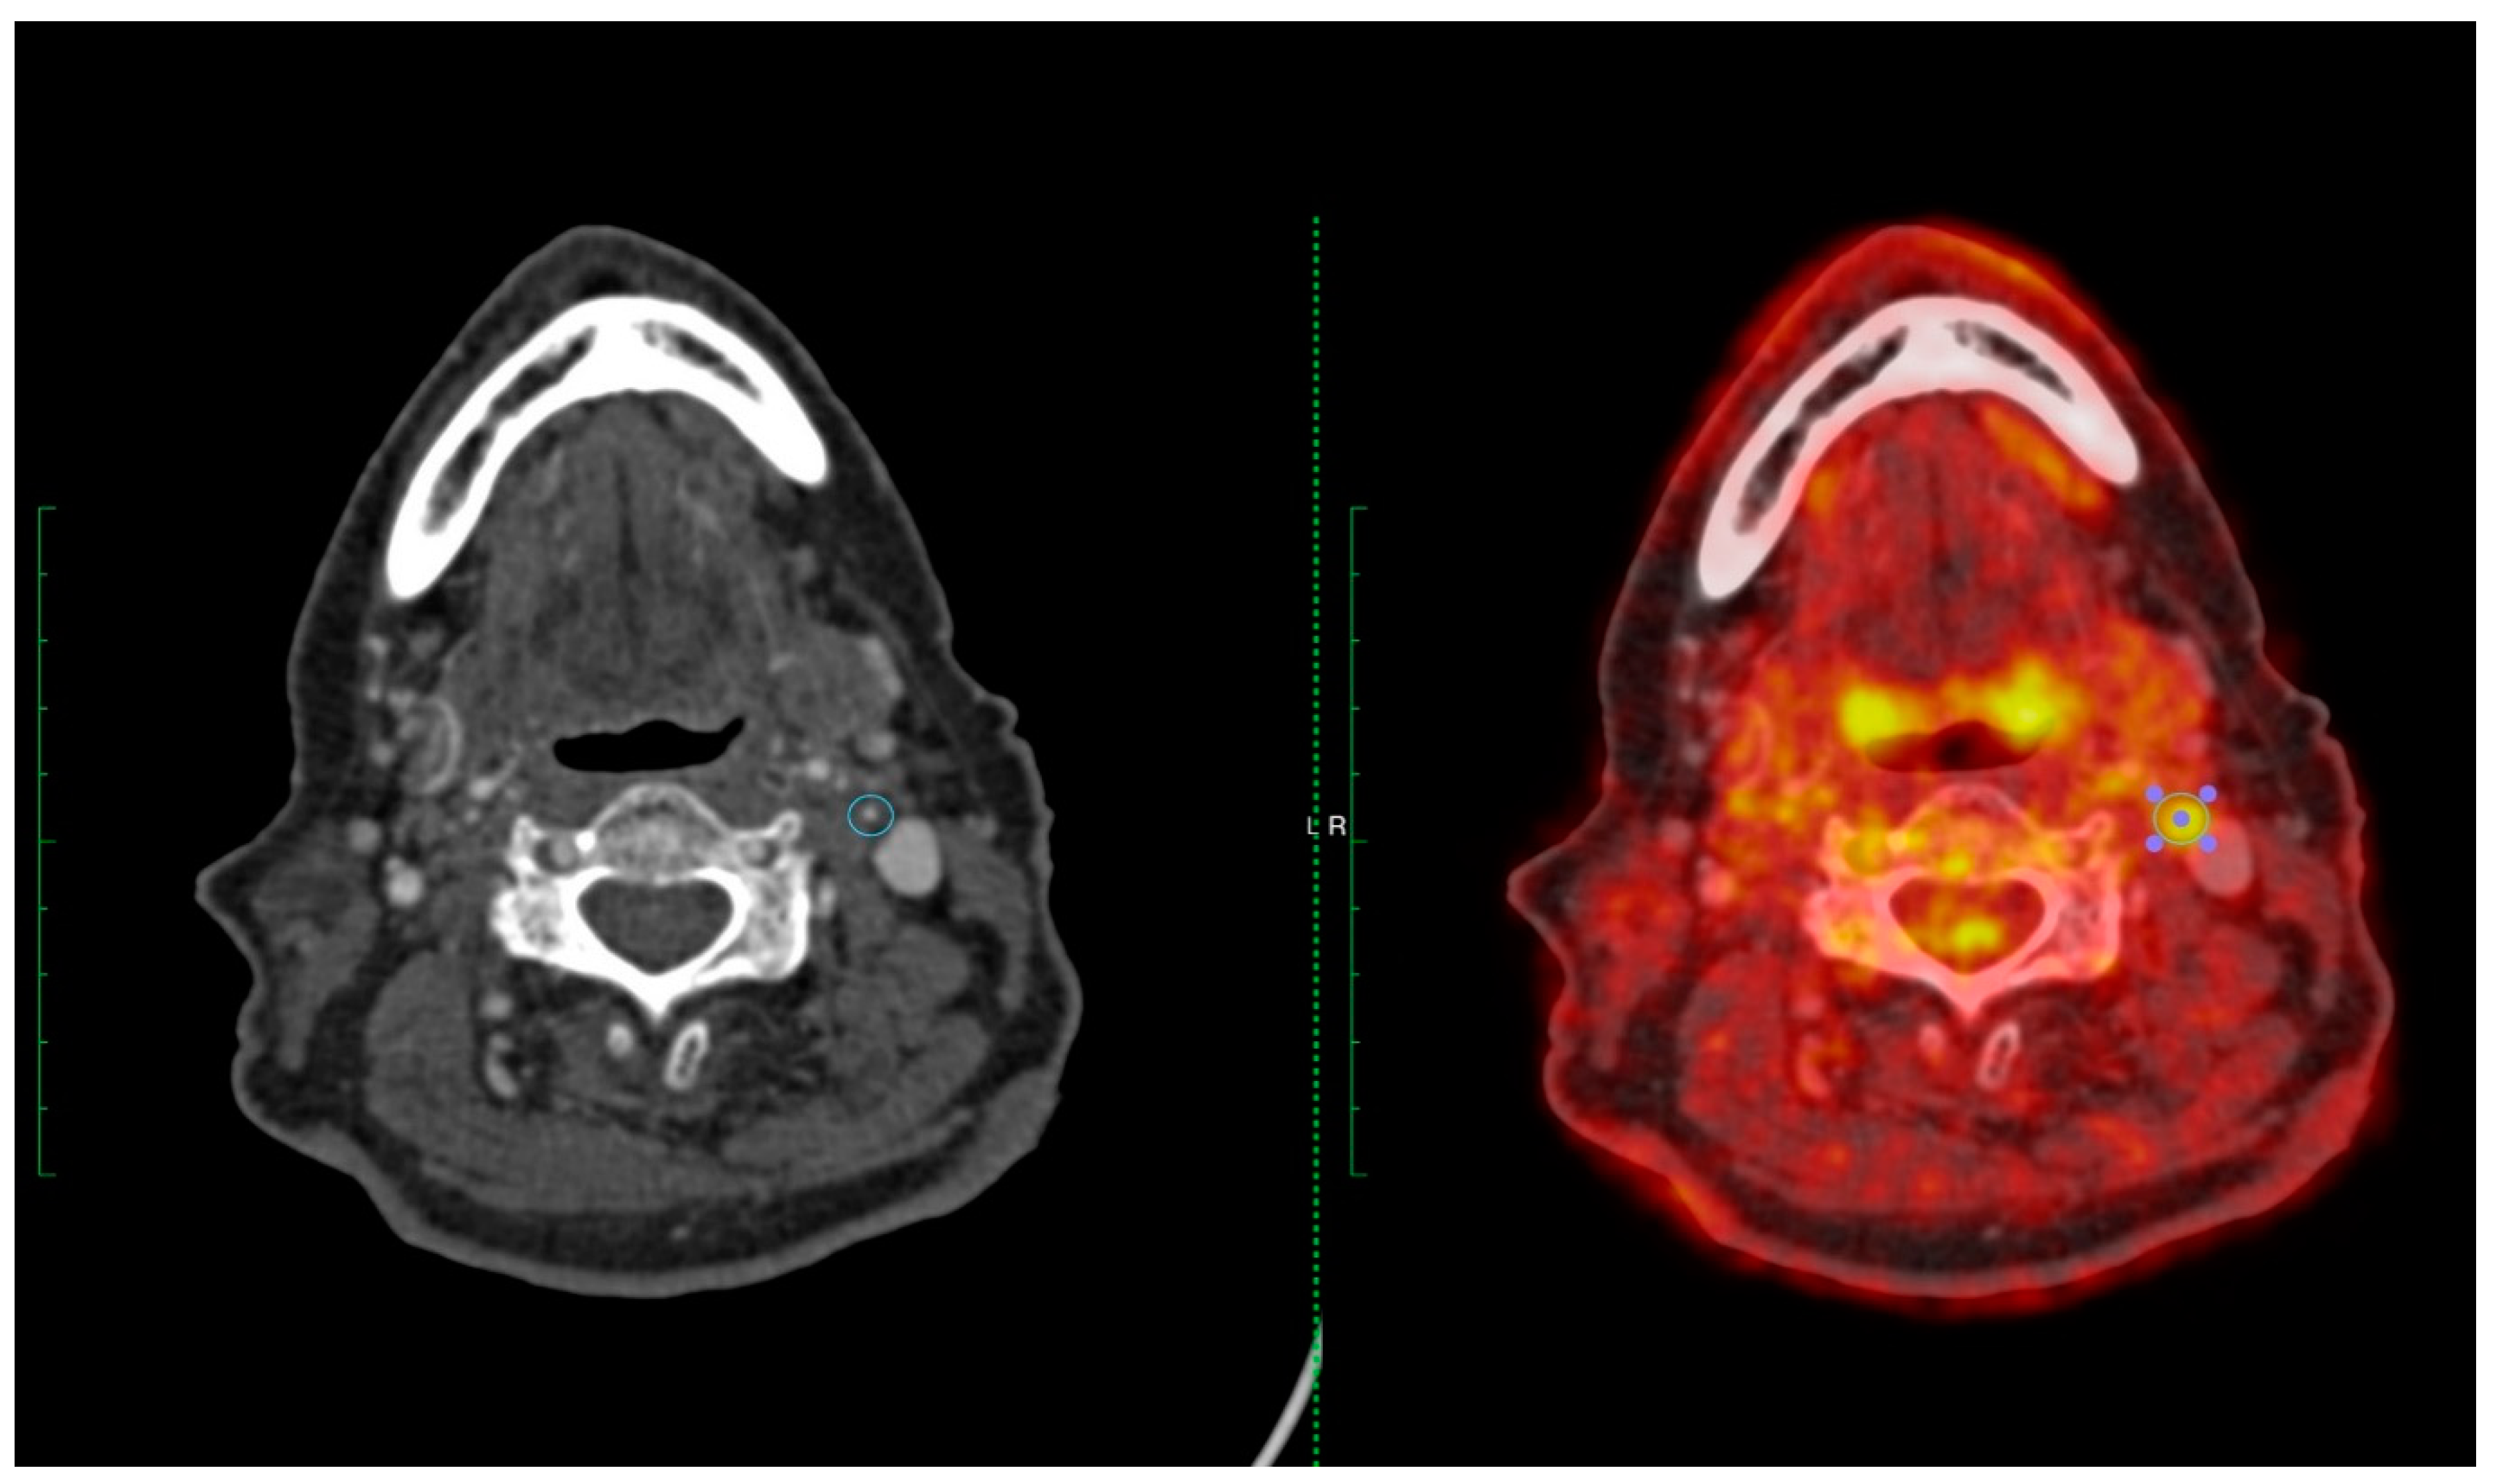

- Marnane M, Merwick A, Sheehan OC, et al. Carotid plaque inflammation on 18F-fluorodeoxyglucose positron emission tomography predicts early stroke recurrence. Annals of neurology 2012, 71, 709–18. [Google Scholar] [CrossRef] [PubMed]

- Kelly PJ, Camps-Renom P, Giannotti N, et al. Carotid Plaque Inflammation Imaged by (18)F-Fluorodeoxyglucose Positron Emission Tomography and Risk of Early Recurrent Stroke. Stroke 2019, 50, 1766–73. [Google Scholar] [CrossRef] [PubMed]

- McCabe JJ, Camps-Renom P, Giannotti N, et al. Carotid Plaque Inflammation Imaged by PET and Prediction of Recurrent Stroke at 5 Years. Neurology 2021, 97, e2282–e91. [Google Scholar] [CrossRef]

- Kelly PJ, Camps-Renom P, Giannotti N, et al. A Risk Score Including Carotid Plaque Inflammation and Stenosis Severity Improves Identification of Recurrent Stroke. Stroke 2020, 51, 838–45. [Google Scholar] [CrossRef]

- Camps-Renom P, McCabe J, Marti-Fabregas J, et al. Association of Plaque Inflammation With Stroke Recurrence in Patients With Unproven Benefit From Carotid Revascularization. Neurology 2022, 99, e109–e18. [Google Scholar] [CrossRef]